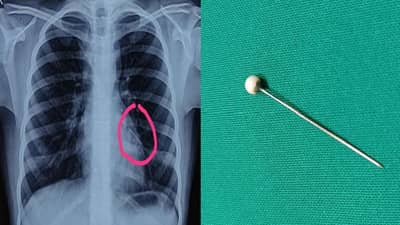

नायरा शहा (नाव बदललेलं आहे) हिने दोन वर्षांपूर्वी खेळताना अचानक एक धातूची पिन गिळली. कुटुंबियांना हे कळल्यावर त्यांनी तातडीने मुलीच्या पोटाचा एक्स-रे काढला. या वैद्यकीय चाचणीतून काहीही आढळून आले नाही. चाचणी अहवालात काहीच दिसून न आल्याने सर्वजण चिंतामुक्त झाले. कालांतराने तिचे कुटुंबीय ही घटना विसरूनही गेले. मात्र, दीड वर्षानंतर मुलीला वारंवार खोकल्याचा त्रास जाणवू लागला. मुलीची प्रकृती पाहून कुटुंबियांनी तिला झेन रूग्णालयात दाखल केले.

रूग्णालयातील कान-नाक-घसा शल्यचिकित्सक डॉ. शाह यांनी सांगितलं की “या मुलीच्या छातीचा एक्स-रे काढला असता तिच्या छातीच्या डाव्या बाजूला खाली वायूमार्गाच्या भागात पिन आढळून आली. ही पिन शोधण्यासाठी छातीचा सीटीस्कॅन काढण्यात आला. त्यानंतर ब्रॉन्कोस्कोपीद्वारे फुफ्फुसात अडकलेली ही पिन बाहेर काढण्यात आली.”